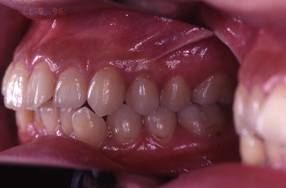

上顎前突+叢生 抜歯矯正(治療期間1年)

治療前、特に上の歯並びに問題がありました

奥歯のかみ合わせもよくありません

口元が突出しています

治療後、正中線も揃いました

小臼歯を抜歯しました

きちんと噛んでいます

大変きれいな横顔になりました。もともと明眸でしたので、矯正治療で明眸皓歯になりました。